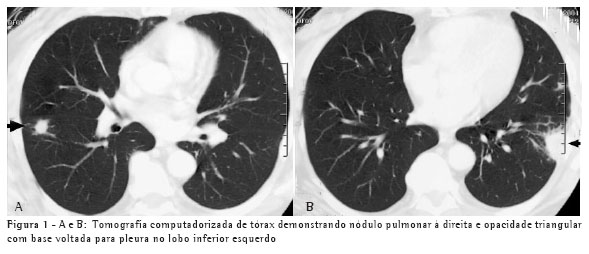

Um paciente, do sexo masculino, branco, de 50 anos, procedente de Blumenau, pedreiro, iniciou quadro semelhante e simultâneo ao do caso 1, dez dias após a limpeza da área referida com presença de fezes de morcego, ficando exposto a grande quantidade de poeira em ambiente fechado. Esteve hospitalizado por sete dias. O aspecto radiológico do tórax, apresentando micronódulos difusamente distribuídos em ambos os pulmões, e o controle evolutivo são demonstrados nas Figuras 2A e 2B.

conhecimento das síndromes clínicas e a suspeição clínica podem evitar o tratamento empírico. Os achados radiológicos, os exames negativos e a alta freqüência da tuberculose em nosso meio foram os fatores para o tratamento para tuberculose nos dois pacientes. O teste de imunodifusão, embora negativo nestes dois pacientes, tem alta sensibilidade, sendo positivo em aproximadamente 75% dos casos.(6) O tempo de exposição ao inóculo determina a gravidade da doença. Isto explica o fato de o segundo paciente, que varreu o local, ter apresentado uma forma mais grave da doença, com alteração radiológica pulmonar difusa e necessidade de hospitalização. Por outro lado, uma pequena exposição determina lesões pulmonares focais, como no caso 1.